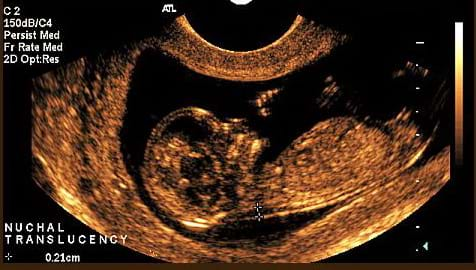

Pregnancy is an exciting time in your life. Dr Hardas is a skilled obstetrician with more than 20 years experience in managing high and low risk pregnancies. Dr Chen has trained in the largest tertiary obstetric hospitals in both Sydney and Melbourne managing both complex and low risk pregnancies with over 10 years of experience. Your obstetrician along with their team of expert midwives will provide care for you during your pregnancy. At the first consultation a detailed medical history will be taken and an ultrasound will be performed to confirm that your pregnancy is progressing normally. Routine antenatal blood tests including thyroid function, Vitamin D & iron levels will be ordered. A urine sample will be collected for analysis to check for protein, glucose and infection. Your obstetrician will discuss non-invasive testing for chromosomal disorders (such as Down Syndrome), They will arrange either a Nuchal Translucency (NT) ultrasound at about 12 weeks or a NIPS (non-invasive prenatal screen) which is performed after 10 weeks. You will be provided with general pregnancy advice such as nutrition, exercise and vitamin supplements. Booking into your preferred Maternity Unit as well as birth classes will be arranged. The frequency of visits is initially monthly and at each consultation you will have your blood pressure, weight and urine checked. Your obstetrician will perform an ultrasound at every consultation to check your baby's progress. |